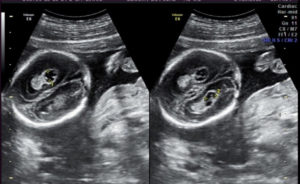

Диагностика проводится еще в утробе с помощью аппарата УЗИ. Специалист может определить кистозные образования, продолжает следить за развитием аномалии в ситуации, когда она не исчезает самостоятельно с 28 недели беременности.

Для новорожденных выполняется нейросонография. Ультразвуковое устройство прикладывается к незаросшему родничку между костями черепа. Процедура в разных роддомах считается обязательной. Только такое обследование позволяет выявить аномалию. После родов нужно проходить повторное обследование, убедиться, не растет ли киста дальше.

Эхографическое ультразвуковое исследование показывает, что киста в головном мозге у плода на сроке 20 недель обычно представляет собой округлое (анэхогенное) образование, обладающее четкими контурами.

Чаще локализуется в системе боковых желудочков. Кисты в зоне сосудистых сплетений в боковых желудочках, расположенных в головном мозге у плода, бывают справа и слева, односторонними и двухсторонними, единичными и множественными.

В течение длительного времени кистозное новообразование может протекать бессимптомно. Первый раз оно, как правило, обнаруживается примерно на 18-ой или на 20-ой неделе беременности при проведении ультразвукового исследования.

На эхограмме киста сплетений представлена в виде контрастных пятен, наполненных жидкостью. Образования имеют небольшие размеры (в некоторых случаях не достигают даже одного миллиметр).

Ультразвуковое исследование позволяет обнаружить очаги поражения сосудистых сплетений, а также контрастные пятна, расположенные среди них. При выявлении новообразований до одного миллиметра, можно сказать, что это, скорее всего, псевдокисты.